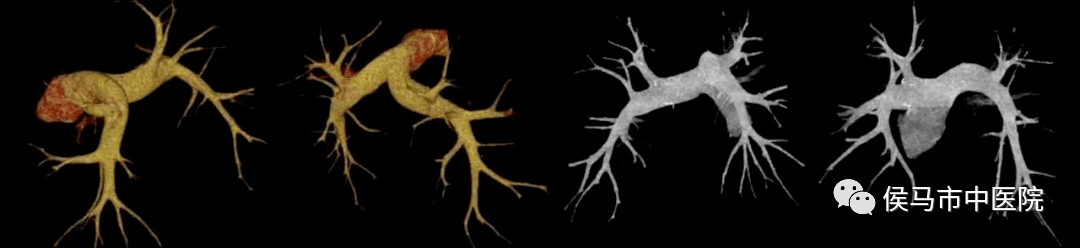

2、肺动脉CT血管造影(CTA)

肺动脉CTA是诊断肺动脉血栓栓塞的重要标准、也是先天性肺动脉发育异常、原发性或原因不明的肺动脉高压及纵隔肿瘤和大血管病变的主要依据,特别是诊断肺动脉血管有无血栓,以及有无血管硬化,准确性特别高,是一种评价肺动脉血管的无创性检查方法。